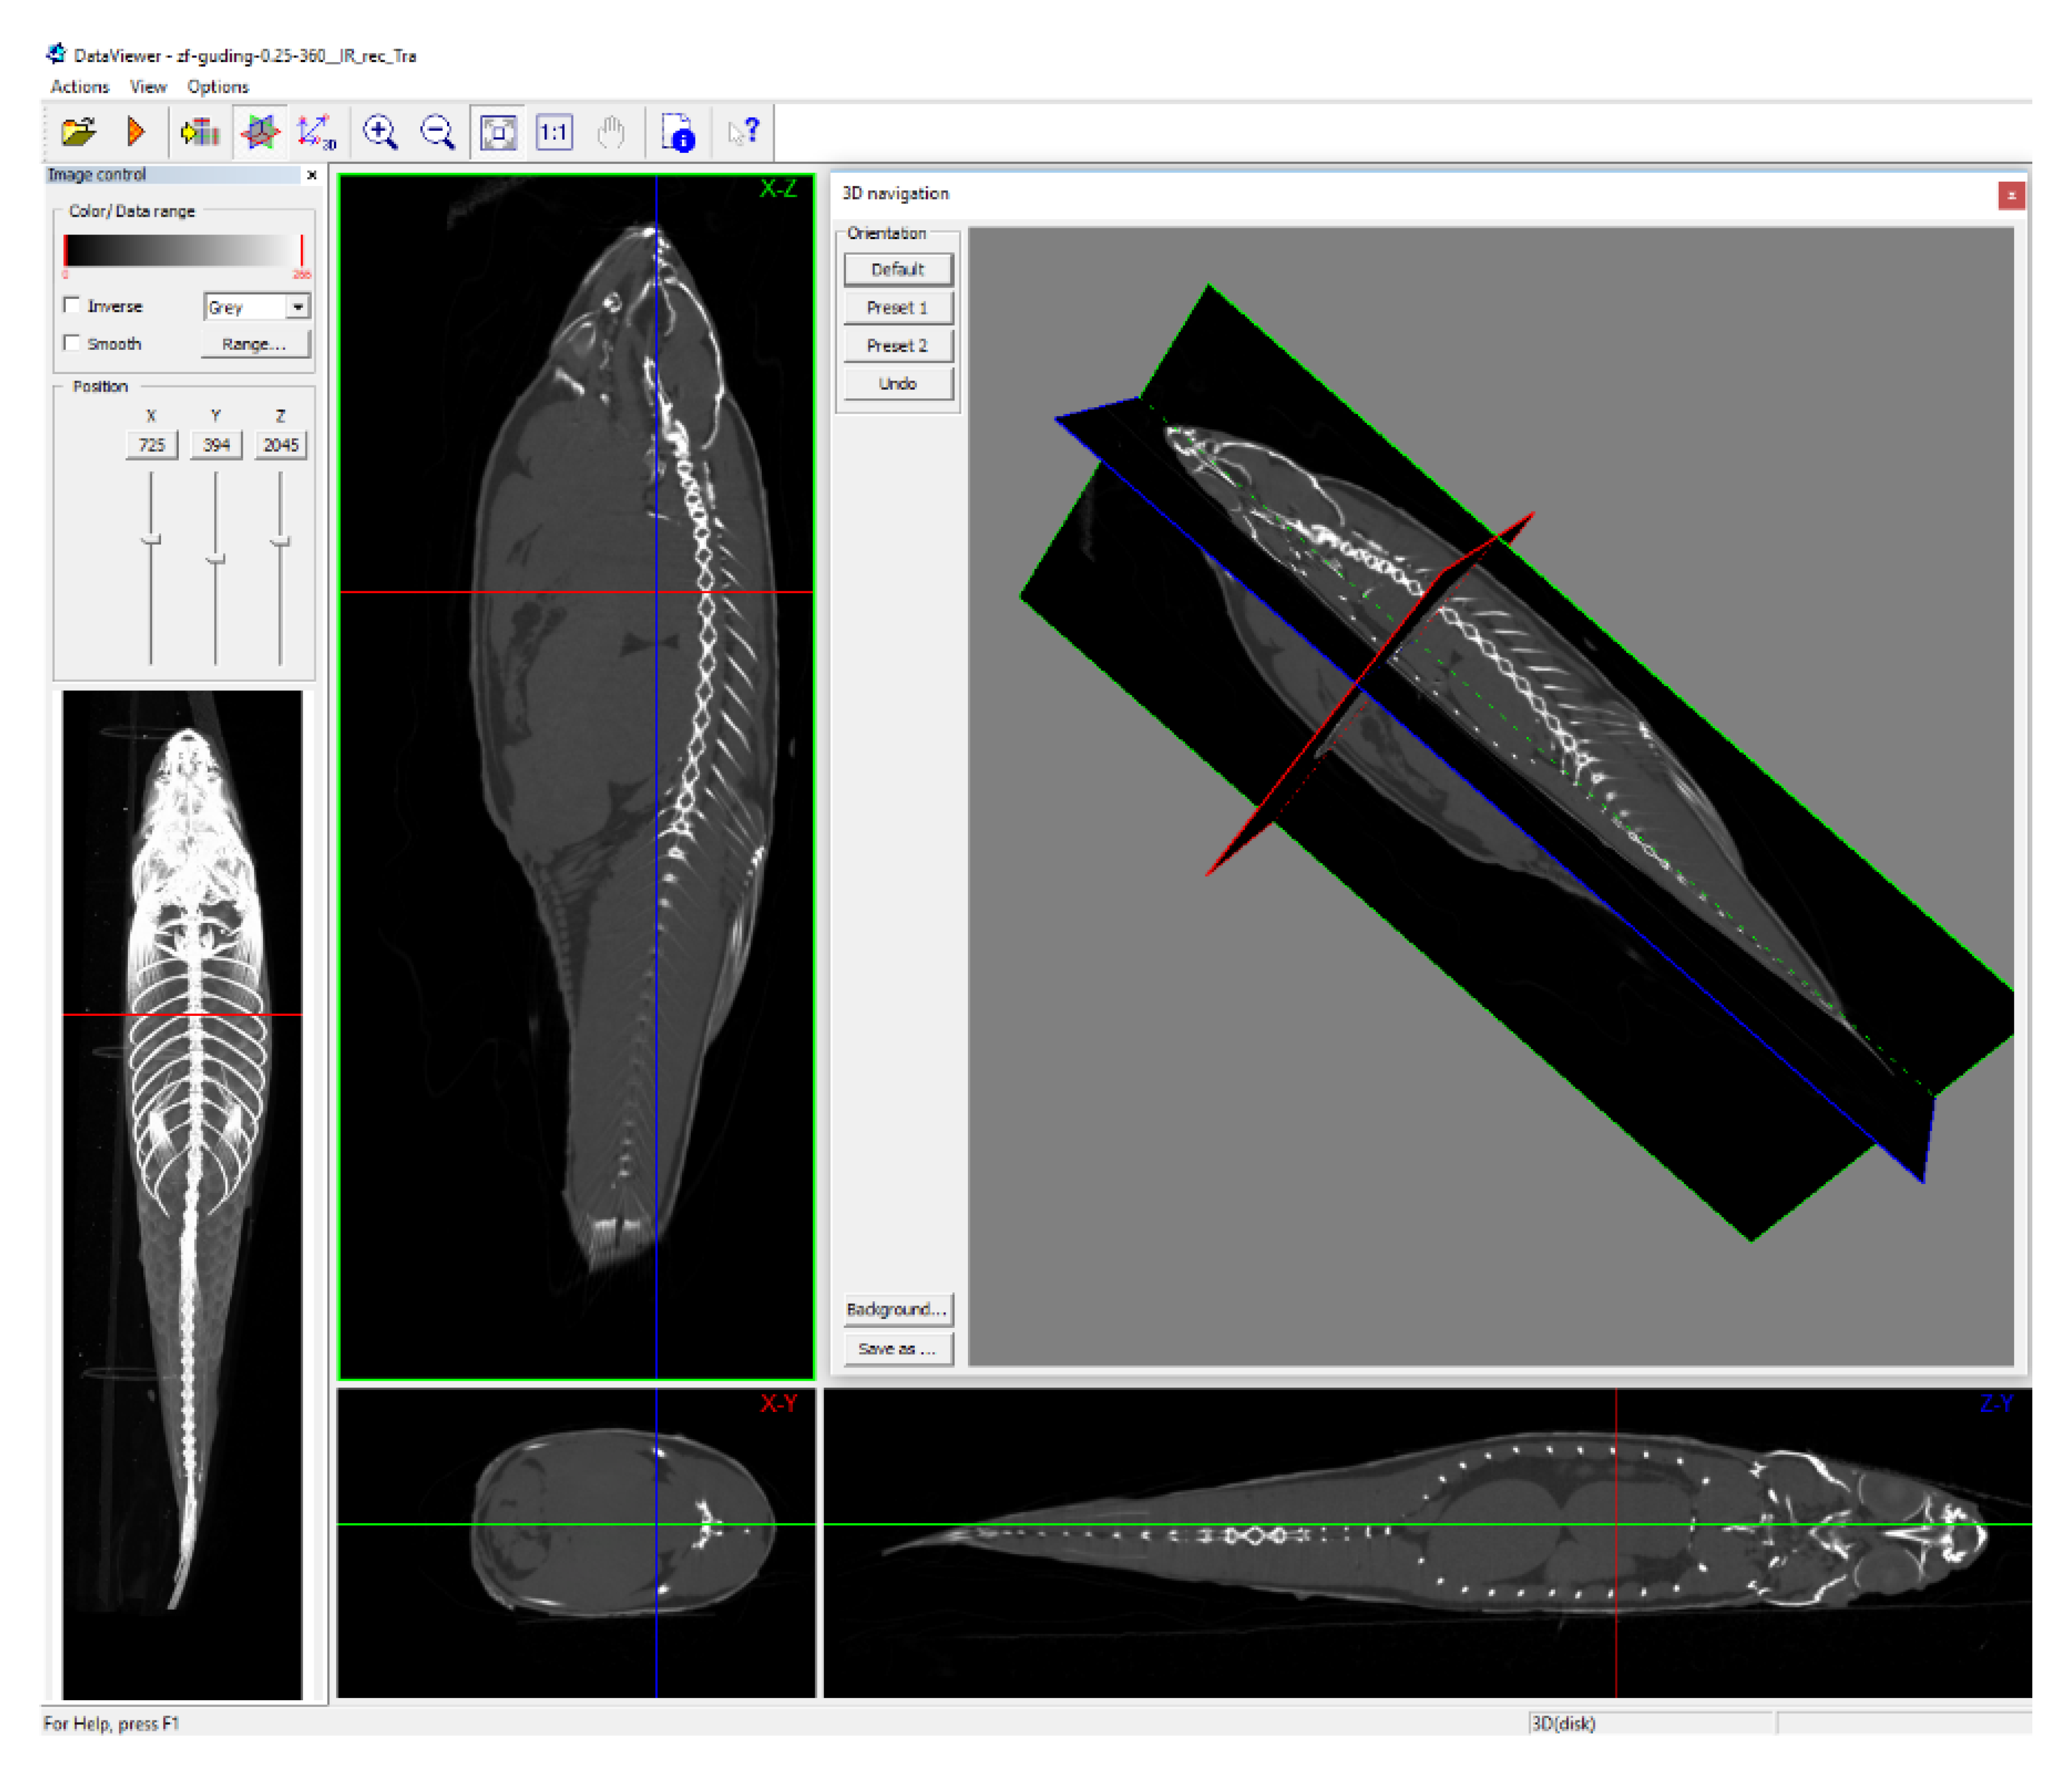

3.1. Method to Detect Adipose Tissue in Zebrafish by CT Scanning

3.2. Distribution of Adipose Tissue in Zebrafish

2.5. Data Processing

2.6. Construction of the 3D Model of Adipose Tissue